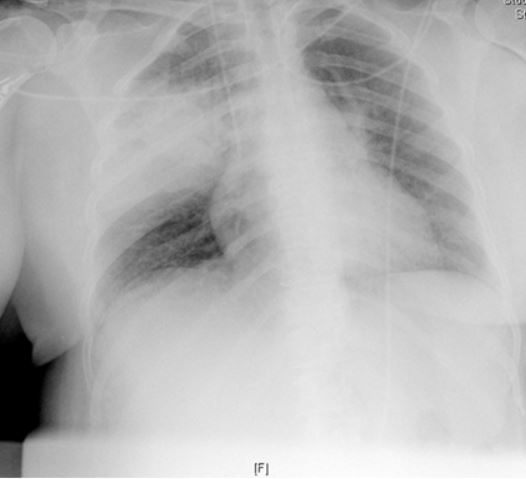

Paciente mujer de 54 años fumadora de un paquete al día desde hace 40 años, con hipotiroidismo primario y síndrome depresivo. Seguida en consultas externas de Ginecología por citología cervical compatible con Lesión epitelial escamosa de bajo grado (LSIL). En el año y medio previo al actual ingreso tuvo 4 episodios de infección respiratoria requiriendo ingreso hospitalario en uno de ellos. Ingresa en UCI por cuadro de disnea, dolor de características punzantes en hemotórax derecho e irradiado a espalda de características pleuríticas. No tos ni expectoración, no fiebre ni sensación distérmica, no ortopnea ni DPN. Refiere en las 3-4 semanas previas un síndrome general con pérdida de peso de 5 Kg. A su llegada a Urgencias la paciente está hipotensa, taquipneica y en gasometría presenta datos de hipoxemia con acidosis metabólica (pH 7,31; pO2 67; pCO2 50; HCO3 2,4). En análisis general destaca: Hb 9,5 g/dl; Leucocitos 8100 cel/ml; Linfocitos 990 cel/ml; Urea 70 mg/dl; Cr: 2,91 mg/dl; Procalcitonina: 25,33 ng/ml. En Rx Tórax se observa una condensación neumónica en LSD (Ver figura). En los hemocultivos crecen cocos gram positivos en diplos y cadenas cortas. En lavado broncoalveolar se observan quistes y trofozoitos característicos. Se realiza test serológico específico que resulta positivo.

CASO CLÍNICO DEL MES DE DICIEMBRE (Cerrado. Ver solución y lista de ganadores) Paciente de 46 años sin antecedentes médico-quirúrgicos de interés, ex-fumador desde hace un año sin otros hábitos tóxicos. Originario de Venezuela lleva residiendo en España tres meses cuando consulta en Junio 2011 por un cuadro de una semana de evolución caracterizado por una disnea progresiva hasta hacerse de pequeños esfuerzos, con tos ocasional no productiva y rinorrea blanquecina, fiebre de 39º, sin dolor torácico ni edema en extremidades inferiores. Refiere que desde un año antes presenta anorexia y pérdida de peso importante. En la exploración física destaca un aceptable estado general, TA: 98/70, Tª 36,2º, Pulso 107 lpm, taquipneico a 20 rpm con Saturación basal del 93%. En cara presenta una dermatitis seborreica severa, en la lengua se observan placas blanquecinas en los bordes compatibles con una leucoplasia vellosa, en la auscultación pulmonar se objetiva una hipoventilación generalizada y el paciente tiene varios tatuajes además de lesiones cutáneas de rascado y pústulosas en piernas y tórax. En la analítica destaca una linfopenia de 900 cel/µL y Hb de 12,9 g/dl y en la gasometría arterial pH 7,48; pO2 53 y pCO2 31. En la radiografía de tórax se describe una enfermedad intersticial difusa de predominio perihiliar que se extiende hacia las regiones subpleurales y es confluente en algunas areas. (Figuras 1 y 2). Se solicita una serología de VIH y una broncoscopia de cuyos resultados estamos pendientes.